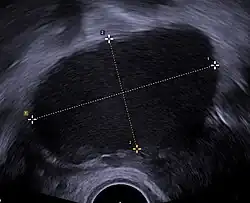

A health history and a physical examination can lead the health care practitioner to suspect endometriosis. There is a clear benefit for performing a transvaginal ultrasound (TVUS) as a first step of testing for endometriosis.[97]

Ultrasound

Vaginal ultrasound can be used to diagnose endometriosis or to localize an endometrioma before surgery.[112] This can be used to identify the spread of disease in individuals with well-established clinical suspicion of endometriosis.[112] Vaginal ultrasound is inexpensive, easily accessible, has no contraindications, and requires no preparation.[112] By extending the ultrasound assessment into the posterior and anterior pelvic compartments, a sonographer can evaluate structural mobility and look for deep infiltrating endometriotic nodules.[113] Better sonographic detection of deep infiltrating endometriosis could reduce the number of diagnostic laparoscopies, as well as guide disease management and enhance patient quality of life.[113]